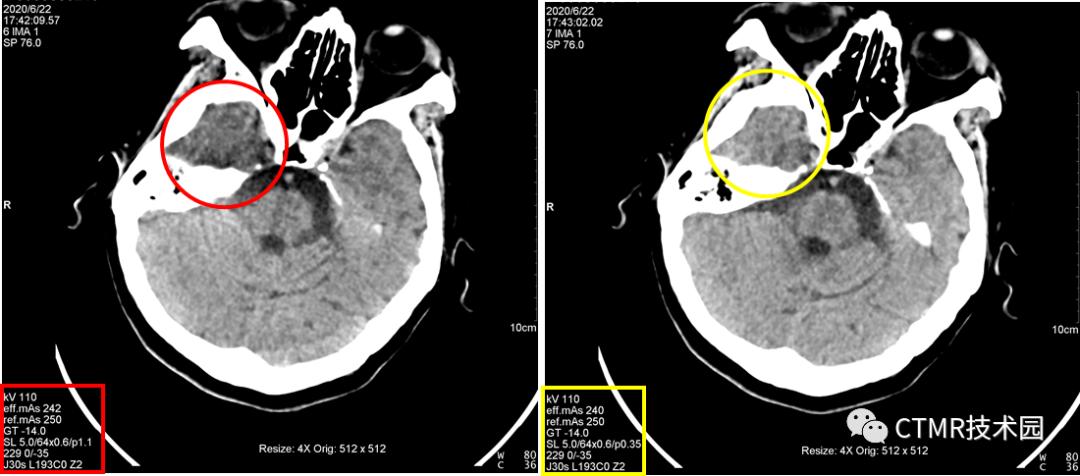

问题1:为什么都是经常出现在右侧呢?因为颅脑大致头足范围都差不多,且都是从头向足螺旋扫描,那么螺旋扫描时可能恰好采集伪影区域层块时,是从头左侧先转的一整圈,那么就导致了右侧不在一个完整的环上,因为转过来时已经跑到下一层块了。其实有时病人以 1.1 螺距扫描是没有伪影的,比如头颅扫描范围有所偏差时,那么上一圈扫描结束位置恰好在前 A 位置,那么伪影这一层块扫描时时恰好左侧与右侧颞部基本都在一整圈范围内。这样的情况也是会出现的,那么此时图像上右侧就不会出现明显的暗区伪影。为了验证如此,我还将扫描顺序更改了下,按足向头扫描(如下图),恰恰暗区伪影经常出现在左侧。当然球管到底是怎么转的,如果能够打开机架外壳,仔细看看就好了。

对比时注意观察图像左下角参数。

而且选用 0.35螺距 eMode 是绿色;如果用 1.1 螺距,那么 eMode 是黄色;如果应用 Adjust,eMode 也变成绿色,且此时当前病人配给的螺距为 0.9,那么它好吗?其实扫描出来的图像大多还是有伪影(从本文开头贴的图片中,有好几个都是 Adjust 后匹配螺距扫描出来的伪影图像)。